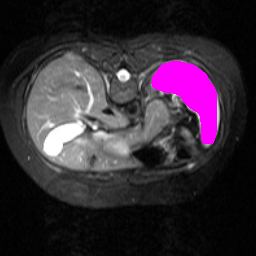

Support

Label

Proposed

In order to assess the performance of the proposed method, we compare the performance of the proposed model with excellent models in recent years. Table 1 and Table 2 shows the comparison results of different models in setting1, while Table 3 and Table 4 shows the comparison results of different models in setting2 on the data set in recent years. PANet[25] is the most widely influential few-shot model in the field of few-shot image segmentation on natural images. SENet [18] is the first few-shot segmentation model proposed for medical images. SSL-ALPNet[19] introduced the milestone of using superpixel self-supervision to train few-shot medical image models. RPNet[29] is a supervised method with a recursive mask optimization module to iteratively optimize the segmentation mask, [27] adapt it into the same self-supervision learning framework and applies setting1 to it and denoted as SSL-RPNet; CRAPNet[27] is the latest SOTA model for 2023. Compared with CRAPNet, our method outperforms most of the state-of-the-art models and only slightly outperforms CRAPNet. Figures 3 and 4 show examples of the model’s segmentation predictions on different datasets, respectively; The first row is the support map, the second row is the label map, and the third row is the segmentation prediction of the model.